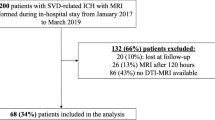

DWI data were corrected for eddy currents prior to DTI fitting using FSL [13]. ROIs for the CST and the PS-CST were obtained using the John Hopkins University [JHU] DTI-based white matter atlas (https://identifiers.org/neurovault.image:1401) (Fig. 1) non-rigidly transformed to each subject’s DWI image space. Similarly, to obtain the ICH and PHE ROIs in each subject’s DWI space, non-rigid transformations were computed between SWI and DWI, and between FLAIR and DWI image spaces. All image transformations were done using the NiftyReg software package [14]. Finally, mean FA and MD were computed in the CST and in the PS-CST using the obtained ROIs. To obtain the ICH probability map, we summed all the lesion masks and divided by the number of patients to give a lesion probability at each voxel.

We included 42 adult patients with spontaneous supratentorial deep ICH (flow chart in Fig. 2). Group probability maps showed the ICH lesion distribution reported in Fig. 3. Table 1 summarizes clinical and radiological characteristics in the entire cohort, including PS-CST mean rFA and rMD. Median age was 62 years (IQR 52–72), and median ICH volume was 5.4 mL (IQR 3.0–11.7). Thirteen patients (31.0%) had poor functional outcome (mRS > 2) at 6 months. Mean rFA was 1.024 (SD 0.139), and mean rMD was 1.046 (SD 0.312). Table 2 describes univariable logistic regression models for the association between clinical and radiological variables, including rFA and rMD, and poor long-term functional outcome.